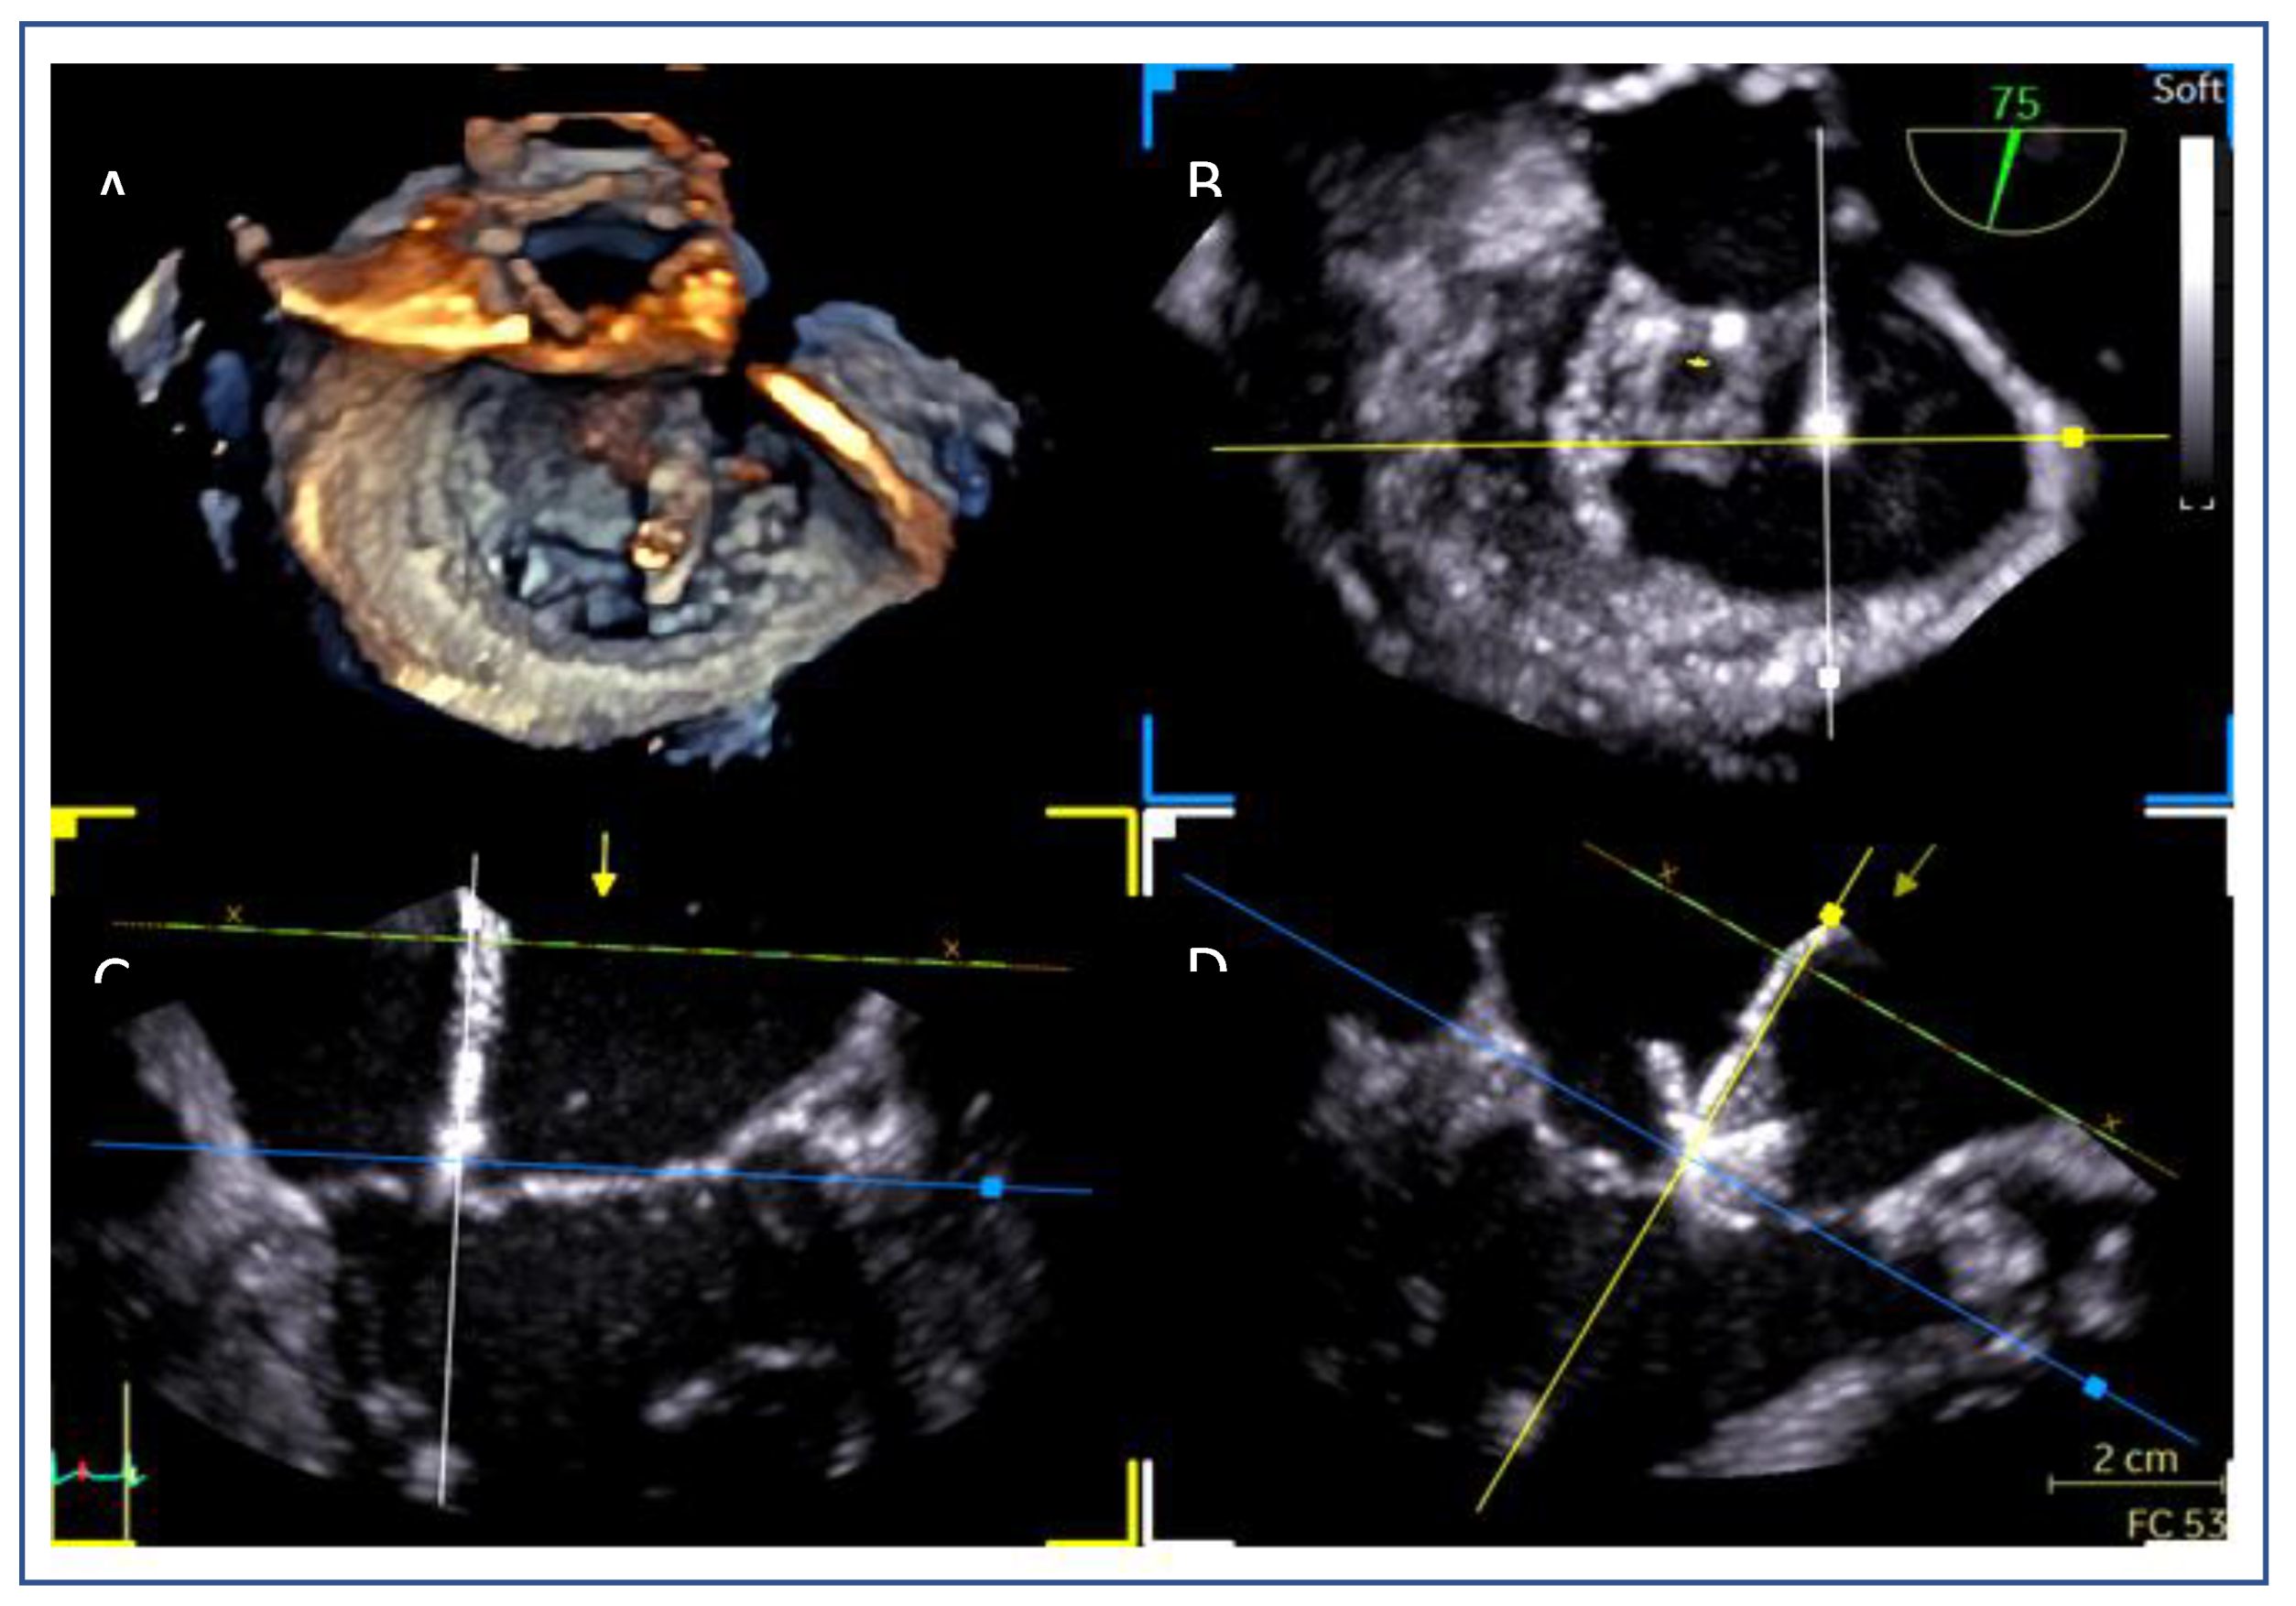

- Lateral commissure: A superior and lower puncture height, approximately 3.5 cm, is preferred to facilitate access.[40]

- Medial commissure: A more inferior puncture, closer to the inferior vena cava (IVC), with a higher height of 4.5–5 cm is recommended for better alignment. [41]

- Ventricular functional MR: The puncture height should be set 1 cm lower than the usual height to match the coaptation depth.[40]